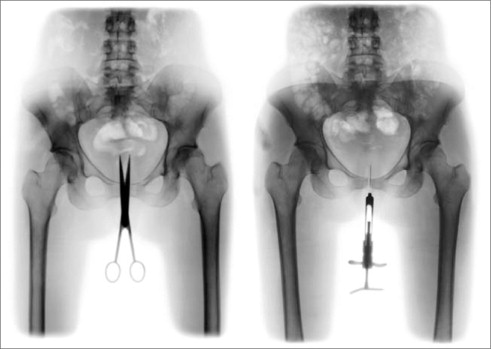

Blanchot escribió que existen dos modalidades de distancia: la distancia que tomamos de las cosas para “mejor disponer de ellas” y la distancia que es “profundidad no viva, indisponible, que se convierte en algo como la potencia soberana y última de las cosas” (O Espaço Literário, 262). Un “utensilio dañado se vuelve su imagen” —observa— “sin desaparecer en su uso, aparece”. Y añade: “Esa apariencia del objeto es la de la semejanza y del reflejo: si se prefiere, su doble”, su cadáver (260). Pero, ¿qué nos sugiere la experiencia contraria? ¿La experiencia de los dobles útiles y disponibles, la experiencia de la sobreposición de las dos modalidades de distancia, del derrumbe de una sobre la otra? Por más de un siglo, la fotografía fue este Atlas que soportaba un cielo de imágenes con los pies firmemente clavados en la tierra de las cosas. No conozco mejor figura de esta condición que la creada por el caricaturista y cineasta francés Cario Rim, en 1930, cuando afirmaba que gracias a la fotografía el ayer se había transformado en un “hoy sin fin”: “Como el hilo que sujeta el globo a la tierra, nuestro sensible aparato nos permite sondear el terreno más difícil, creando un tipo de vértigo particularmente suyo” (“On the snapshot”, 37-38). Ahora, desatadas, incorpóreas, como valquirias digitales, recogen los restos mortales de este fenomenal desmoronamiento. En el crepúsculo de estos restos, en la imagen desencarnada se ve el “reflejo volviéndose señor de la vida reflejada”: se ve el cadáver que “es su propia imagen” (Blanchot, O Espaço Literário, 260). Durante todo el siglo xix , la fotografía fue una poderosa aliada de la agenda iluminista de anexión de lo invisible a los territorios de la visibilidad. Una agenda que pautó la ciencia de los siglos xvii al xix en su lucha incansable contra la oscuridad del mundo, cuyo marco inicial fue la invención del microscopio, y culminó con el registro de las sombras producidas por los rayos X emitidos por un “tubo de Crookes”, en 1895. Sobre la primera de estas radiografías, el inventor Wilhelm Röntgen anotó “fotografía de una mano viva” (fig. 6 ). La fotografía no transponía así solo los límites de la carne, sino los propios umbrales de la muerte. Nunca dejamos de admirarnos que uno de los dedos de la modelo —la propia esposa del científico, Anna Bertha— se encuentre adornado por un anillo, signo de la vanidad de los vivos y de la fidelidad eterna de las parejas. Al contemplarla por primera vez, dicen, la señora Röntgen exclamó: “¡vi mi muerte!”

Wilhem K. Röntgen. La mano de la señora Röntgen, 1895

Figura 6.

Si todo cuerpo muerto es lo vivo reducido a su imagen, su contrapartida es que toda imagen es vida muerta en busca de un cuerpo. Y desde las entrañas indiferenciadas de la nueva imagen, el deseo de cuerpo que las habita encuentra su expresión más punzante. Expresión que no es ya, como señalaba Hannah Arendt, la de la interioridad “de una idea, de un pensamiento, de una emoción”, sino “expresividad de una apariencia”, que no expresa nada a no ser a sí misma (30). En los Retratos íntimos de Cris Bierrenbach (figs. 7 y 8 ), el dolor se vuelve un imperativo de la propia imagen. En tanto que en la “fotografía vaciada” de Dabdab, la sustancia inmaterial de lo digital disuelve las distinciones que solo las palabras de la leyenda insisten en preservar; en estos retratos, materia e imagen están en tensión permanente. Tensión de la que ahora ninguna palabra puede dar cuenta.

Cris Bierrenbach. De la serie “Retrato íntimo”, 2003

Figuras 7 y 8.

La tijera y la jeringa no cesan de convocar a la carne de la imagen y, simultáneamente, frustrar su encarnación. Ya no es necesario decir, como el Dr. Röntgen, que se trata de la “mano viva” de su esposa, cuya devoción un anillo testimonia. Huesos vivos ya nos son familiares y el metal ya no los envuelve, como un pequeño círculo protector: el metal instiga, perfora. De esta nueva condición de las relaciones de las imágenes entre sí (y de la fotografía con el mundo), Roberta Dabdab hizo anamnesis y Cris Bierrenbach el reporte de autopsia: agotada de tanto decir, vaciada de su magia, la fotografía despojada de palabras reencuentra en el grito lacerante el único modo de dar voz a lo real que subsiste en las entrañas de la realidad. Por intermedio de este grito, el cuerpo retorna como la Tierra prometida de las imágenes.